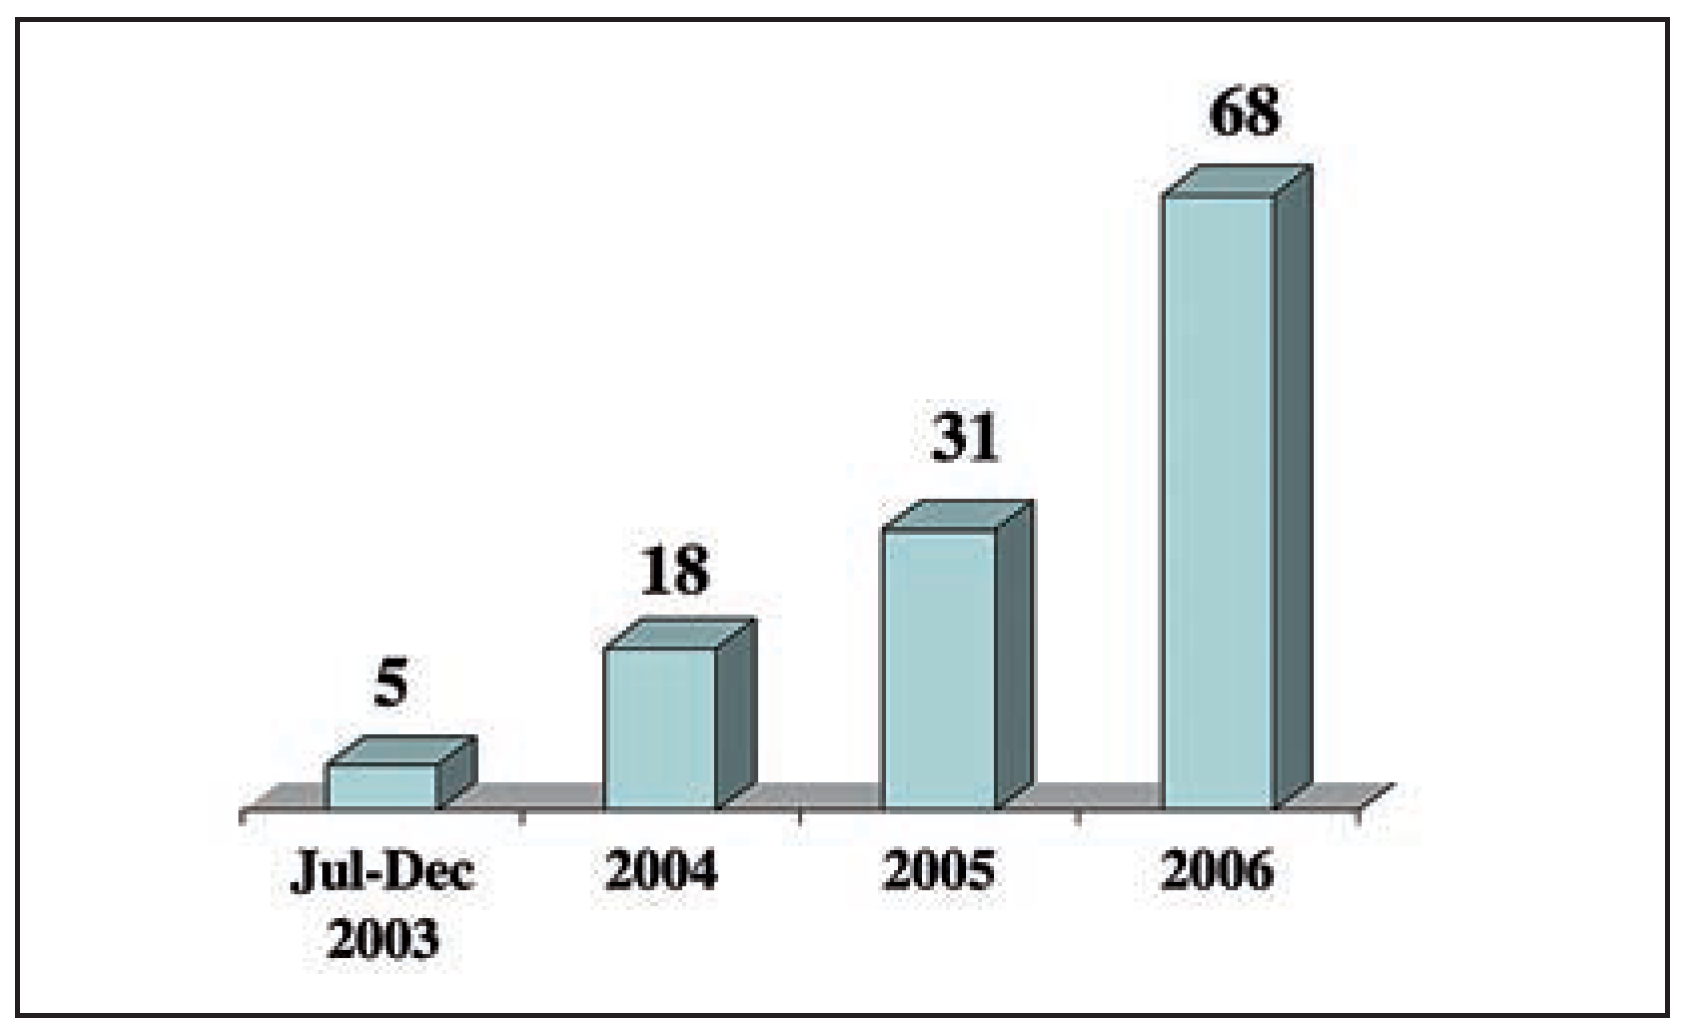

Schliesslich entwickelte sich das Karotis-Stenting zu einem bedeutenden Eingriff für interventionelle Kardiologen. Neue Technologien besonders durch Verwendung von so genannten Filter-Devices zur Vermeidung von zerebrovaskulären Embolien aus rupturierten Plaques haben die Ergebnisse erheblich verbessert. Am UniversitätsSpital Zürich wurden in den letzten Jahren über 140 solche Eingriffe mit einer minimalen Komplikationsrate (30-Tage-Mortalität-, Herzinfarkt- und Schlaganfall-Risiko 2,1%) auch bei Hochrisikopatienten durchgeführt (

Figure 3 and

Figure 4). Diese Ergebnisse machen deutlich, dass sich das Karotis-Stenting heute zu einer Alternative der Karotis-Endarterektomie entwickelt hat.